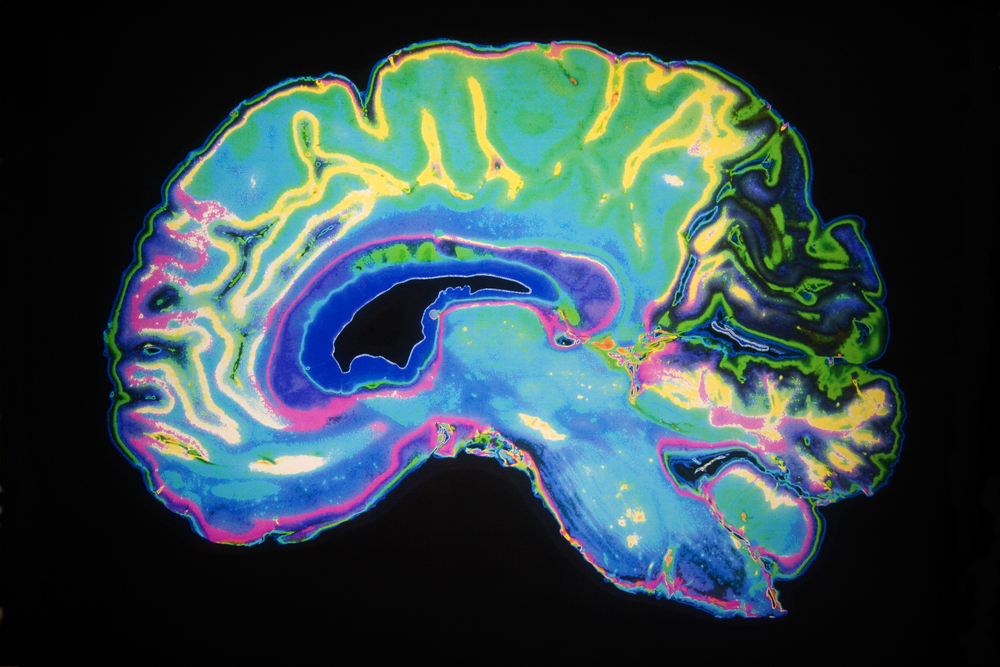

Η αμερικανίδα ανθρωπολόγος Ελεν Φίσερ περιγράφει την εμμονική προσκόλληση που βιώνουμε σε κατάσταση έρωτα σαν «κάποιος να έχει κατασκηνώσει στον εγκέφαλό μας». Σε ένα πρωτοποριακό πείραμα, γράφει ο Guardian, η Φίσερ και οι συνεργάτες της στο Πανεπιστήμιο Stony Brook στην πολιτεία της Νέας Υόρκης έκαναν μαγνητική τομογραφία στους εγκεφάλους 37 ανθρώπων που ήταν τρελά ερωτευμένοι.

Και έδειξαν ότι η ρομαντική αγάπη προκαλεί έντονη δραστηριότητα σε περιοχές του εγκεφάλου που είναι πλούσιες σε ντοπαμίνη, την χημική ουσία του εγκεφάλου που μας κάνει να νιώθουμε καλά. Παρόμοιες περιοχές του εγκεφάλου «φωτίζονται» κατά τη διάρκεια της ευφορίας, που προκαλεί η λήψη κοκαΐνης.